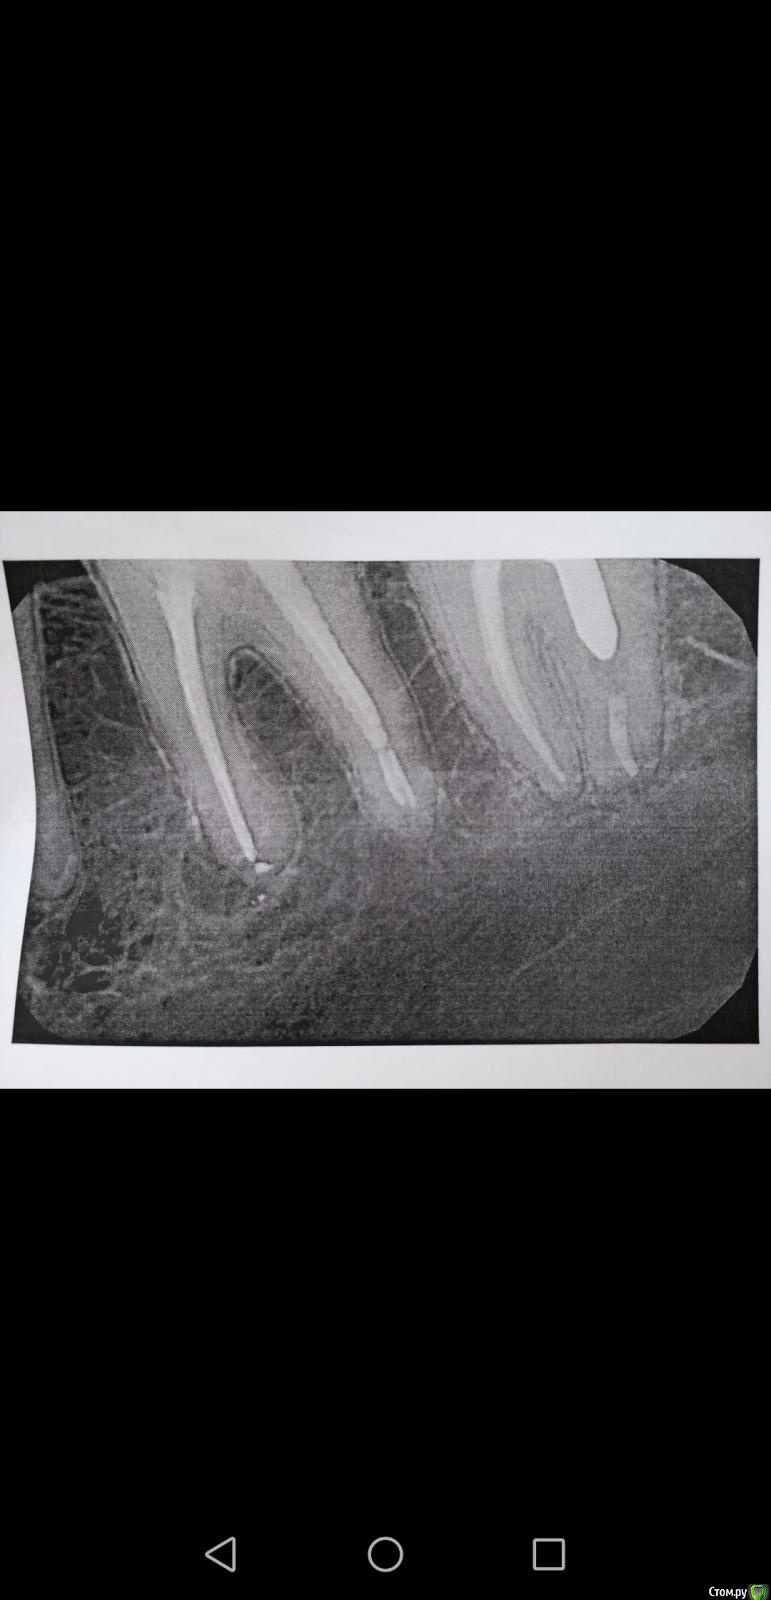

Libelle888 Опубликовано 31 августа, 2019 Поделиться Опубликовано 31 августа, 2019 Добрый день. Пару дней назад начал болеть угол нижней челюсти, потом добавились мышцы и та же половина челюсти, боль ноющая, плавающая, то сустав то щека то десна то кость, конкретно место определить сложно, болезненные лимфоузлы. У меня там есть коронка, установленная 3 месяца назад и давно депульпированный зуб, на котором киста уже давно. Сделала снимок, но к терапевту запись только на понедельник. Жевать не больно, даже наоборот боль затихает когда ем или жую жвачку. При постукивании тоже боли нет. Подскажите, может ли быть причиной таких болей один из этих зубов? И ещё такой момент, заметила, что по ночам и днем тоже непроизвольно сжимаю челюсть Ссылка на комментарий

Libelle888 Опубликовано 31 августа, 2019 Автор Поделиться Опубликовано 31 августа, 2019 Добрый день. Более вероятны проблемы с суставом. Обязательно посетите доктора для очного осмотра. посмотрео ортопед, сустав щёлкает, но он сказал нет там такого чтобы давать какие то боли ощутимые.. Сказал вероятнее все таки какой то зуб. По поводу кисты сказал делать кт, возможно она передавливает тройничный нерв, тк по описанию больше похоже на тройничный нерв... Только причём тут тогда лимфоузлы (( Ссылка на комментарий